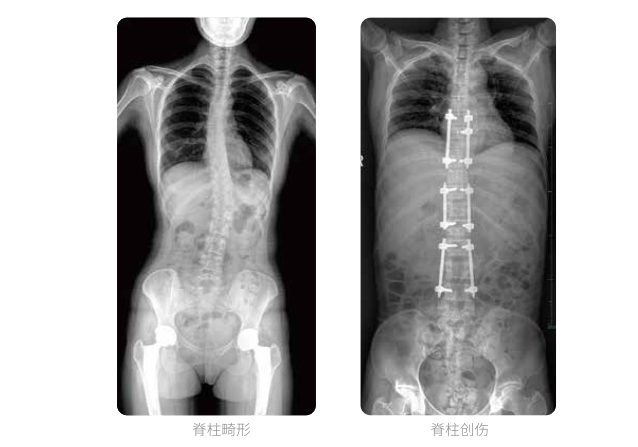

全脊柱臨床影像

PLX8600大視野平板動(dòng)態(tài)DR全脊柱一次成像攝片適用于兒童、成人、老年人腰椎退行性病變、強(qiáng)直性脊柱炎、脊柱結(jié)核等臨床應(yīng)用,在此類大視野的臨床拍攝中發(fā)揮了極大的價(jià)值。

PLX8600大視野平板動(dòng)態(tài)DR可在透視情況下多角度觀察病灶部位,做術(shù)前診斷及術(shù)后愈合的檢查,如脊柱斜位透視,可觀察椎弓根峽部,診斷椎體是否滑脫等情況;可在脊柱運(yùn)動(dòng)狀態(tài)下通過透視模式觀察全脊柱狀態(tài),了解病變處脊柱的活動(dòng)度及骨結(jié)構(gòu)的關(guān)系,配合點(diǎn)片功能快速獲得高清的關(guān)鍵幀影像,輔助醫(yī)生制定更準(zhǔn)確的手術(shù)方案。